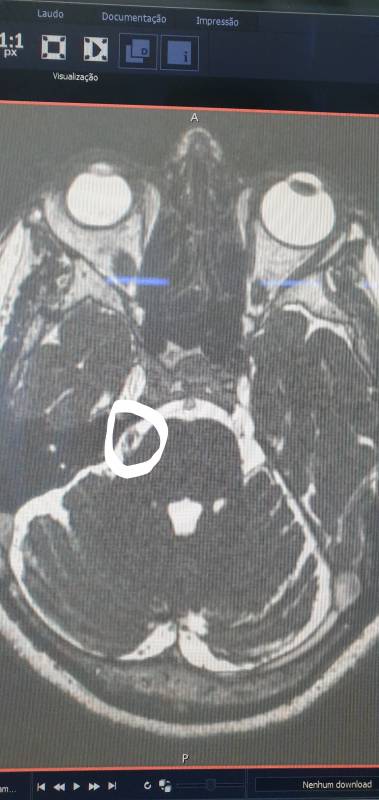

Os exames de imagens são realizados para afastar que a compressão seja por arterias cerebrais, assim, dependendo da causa podemos planejar nosso tratamento de forma mais segura e mais objetiva. A ressonância magnética de crânio é o melhor exame para avaliarmos as causas, quando existam, da TN.